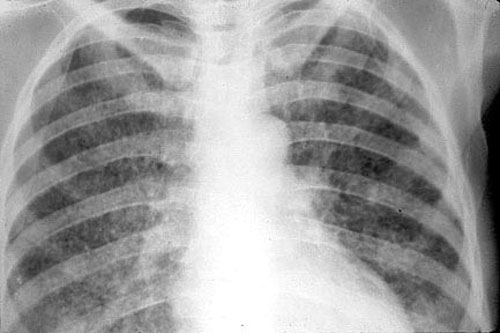

Рентген

Опасным воспалением при туберкулезе или пневмонии считается верхнедолевой очаг поражения, который чаще всего поражается микобактериями.

При пневмонии обнаруживаются на рентгене изменения, позволяющие отличить ее от туберкулеза:

- Уплотнение (инфильтрация) участка легких с неявными, размытыми очертаниями или в виде дымки (характерно для снимков при острой форме).

- Усиление легочного рисунка (при интерстициальной форме).

При верхнедолевой левосторонней пневмонии поражается до 5 долей легкого. Заболевания этого органа протекают тяжелее, чем правосторонняя пневмония, при которой поражается 1-3 участка.

Флюорографией при пневмонии чаще выявляется поражение нижних и средних частей с изменениями корня легкого.

При туберкулезном инфицировании изменения отмечаются в верхней части легкого, отличаются четкими очертаниями, без видимых изменений корня.

На рентгенограмме обнаруживается при туберкулезе:

- Диссеминированном. Множество мелких, хорошо очерченных, или более крупных пятен, есть каверны.

- Очаговом. Уплотнение находится не ниже 2 ребра, вокруг могут быть фиброзные тяжи, усилен легочный рисунок.

- Инфильтративном. Уплотнения правильной округлой формы на рентгеновском снимке в верхней легочной доле.

- Казеозной пневмонии. Множество полостей распада с неровными краями, очагами отсева, смещением средостения в больную сторону груди.

Рентгеновские снимки на сегодняшний день являются самым надежным методом в постановке диагноза заболеваний легких. Их поражение присутствует в обоих случаях, однако картина существенно различается.

Рассмотрим основные отличия этих заболеваний на снимках:

- Локализация поражений легочной ткани. При пневмонии инфильтративные тени, характеризующие очаги поражения, просматриваются, как правило, в 3, 4, 5, 7, 8, 9 долях легкого, преимущественно поражая нижние участки. Туберкулез, в свою очередь, имеет одностороннюю локализацию, в большинстве случаев поражая правую долю легких в 1, 2, 6 сегментах.

- Очертания теней. При пневмонии инфильтраты (рентгеновские тени) имеют размытые, нечеткие очертания. В острый период заболевания затемнение напоминает дымку, а по мере развития воспаления интенсивность теней возрастает, но нечеткий характер краев сохраняется. Туберкулез же имеет тени с выраженным четким рисунком.

-

Форма теней. Очаги поражения при пневмонии, как правило, округлой, неправильной, кольцевидной или веретенообразной формы. Площадь поражения зависит от формы заболевания:

- очаговые тени имеют белый цвет и в диаметре не превышают полутора сантиметров, бывают в начале заболевания или при выздоровлении,

- долевая форма характеризуется полным поражением доли легкого,

- сегментарные тени – инфильтрация определенного сегмента,

- крупозная форма – самый тяжелый вариант, при котором воспаляются оба легких, сопровождается различными множественными очагами теней с обеих сторон органов.

Инфильтраты при туберкулезе зависят от формы данного заболевания:

- Диссеминированный туберкулез сопровождается множественными мелкими очагами до 2 мм в диаметре,

- Очаговый , имеет один или несколько теней округлой, эллиптической, реже вытянутой формы с низкой интенсивностью, при которой очаги поражений темнее костной ткани,

- Казеозная форма является самой тяжелой и сопровождается затемнением нескольких долей или даже целого легкого, тень изменяется по мере распада от менее интенсивной до более выраженной,

- Кавернозный , характеризуется очаговым затемнением с просветом посередине (каверна).

Как правило, при постановке диагноза туберкулеза с помощью рентгена необходимо уметь отличать его от рака легкого и пневмонии. Часто разницы на снимках пневмонии и туберкулеза, особенно при инфильтративной форме, практически нет. Однако есть и некоторые отличия. Пневмония обычно представляет собой одностороннее поражение, в то время как туберкулез в большинстве случаев поражает легочную ткань с двух сторон.

Кроме того, инфильтрат при пневмонии локализуется в нижних отделах, а при туберкулезе — в верхних. Инфильтрат более выражен при туберкулезе, часто имеются очаги деструкции, диссеминации.